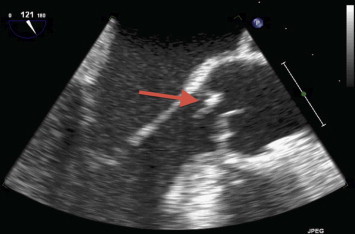

A transthoracic echocardiogram showed severe aortic regurgitation with decreased left ventricular ejection fraction of 40%. A subsequent transesophageal echocardiogram demonstrated a mobile echodensity on the non-coronary cusp of the aortic valve prolapsing into the left ventricle outflow tract (Fig. 1). There was severe aortic valve regurgitation associated with holodiastolic flow reversal in the descending thoracic aorta (Fig. 2). The echocardiographic findings along with the patient's blood culture results are consistent with aortic valve endocarditis.

Fig. 1.

Transesophageal echocardiogram demonstrating (arrow) a mobile echodensity on the non-coronary cusp of the aortic valve prolapsing into the left ventricle outflow tract.